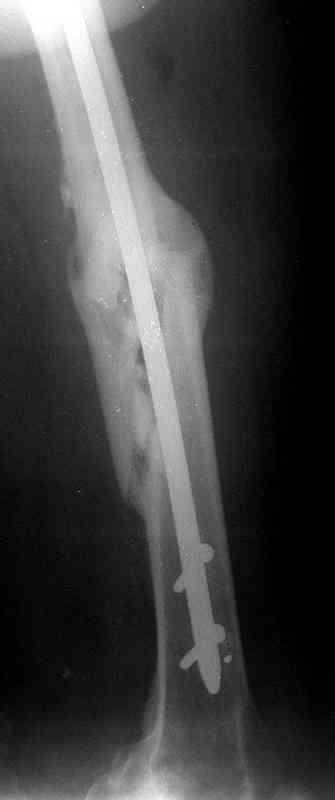

Сувалян Микаэл 01 Апрель 2007, 14:01

Вчера, когда написал свое сообщение, решил еще раз открыть фоторентгенограмму и убедиться в правильности своих суждений на счет общепринятого интрамедуллярного остеосинтеза. Попытка была безуспешна:)

Сегодня фотография открылась...беру свои слова назад: перелом явно в расширенном участке бедра. Целесообразней всего динамический блокирующий остеосинтез.

Учитывая смещения отомков по длине (хоть и 1,5 см, но все же..), очевидное ротационное смещение (видно даже по Р-мам) самым правильным, на мой взгляд, решением было бы: наложение аппарата Илизарова на бедро с остеотомией бедренной кости и исправлением ротационной деформации. Дистракция на аппрате пару недель и последующий блокирующий остеосинтез. У нас в клинике был один пациент с практически идентичной историей (укорочение конечности было значительно больше), которому мы выполнили такую операцию (блокирующий остеосинтез был выполнен без рассверливания костно-мозгового канала). В настоящее время больной работает, прыгает с парашютом, периодически звонит и благодарит за лечение.

Все это, безусловно, трудоемко, как для медперсонала, так и для пациента, но это самый оптимальный вариант (ИМХО).

по его наружной поверхности послеоперационный рубец - рана зажила первичным натяжением. При измерении длины бедер обнаружено укорочение левого бедра на 4,5 см. На рентгенограммах этого бедра: ось конечности правильная, отмечается захождение основных костных фрагментов по длине, проксимальный конец штифта выступает слишком медиально и высоко относительно большого вертела, периостальная мозоль незначительна.22.12 - через 6 месяцев после операции, произведенной в ЦРБ, нами по поводу замедленно консолидирующего перелома левой бедренной кости с ее абсолютным укорочением под наркозом произведена операция: удаление штифта, закрытый блокирующий интрамедуллярный остеосинтез перелома левого бедра штифтом без рассверливания (UFN) длиной 40 см, диаметром 10 мм с блокированием только проксимальных отверстий (динамический остеосинтез). Наложен аппарат Илизарова на 4 полукольцах с целью удлинения укороченного бедра. Послеоперационное течение без особенностей. Ежедневно осуществляли дистракцию отломков на 1 мм. Через 3 недели после операции больной выпи-сан на амбулаторное лечение с продолжением дистракции отломков. В течение 1,5

месяцев дистракции укорочение левого бедра удалось полностью устранить. 22.02.00, т.е. через 2 месяца после повторного остеосинтеза, больному произведено дистальное блокирование штифта двумя винтами и демонтирован аппарат Илизарова. В течение 2 недель после операции больной ходил с помощью костылей, потом 2 недели с тростью. Опороспособность и функция оперированной конечности полностью восстановились через 4 недели после операции.